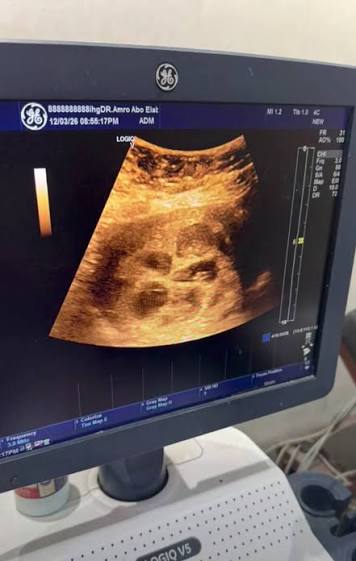

تداولت صفحات التواصل الاجتماعي مقطع فيديو يوثق لحظة كشف طبيب النساء والتوليد على السيدة باستخدام جهاز السونار، حيث ظهر بوضوح وجود 8 أجنة داخل الرحم، فيما شرح الطبيب المشرف تفاصيل الحالة الطبية.

وكشف الدكتور عمرو أبو العباس، استشاري النساء والتوليد، عبر صفحته الرسمية، أن الحمل حدث بشكل طبيعي دون اللجوء إلى وسائل الإخصاب المساعد مثل الحقن المجهري أو أدوية تنشيط التبويض.

وأشار إلى أن الحالة خضعت لبرنامج علاجي دقيق ومتابعة طبية منتظمة، إلى أن حدثت المفاجأة بحدوث حمل طبيعي في 8 توائم، وهو ما يعد من الحالات النادرة جدًا على مستوى العالم.